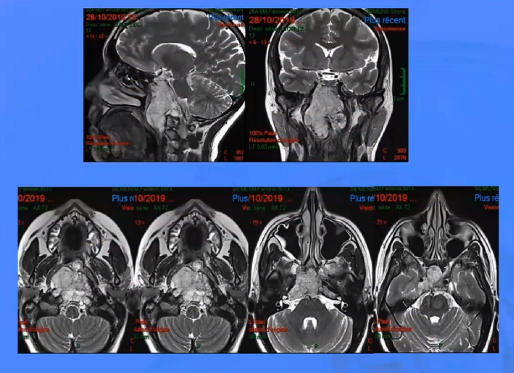

CASE 2

▼下图所示案例肿瘤看着很大,然后用30度、45度甚至70度的内镜,我们有很多带角度的器械,利用这些器械就可以切除肿瘤。可以先切开黏膜,然后把蝶窦内的黏膜推开,然后进入肿瘤。目前我们正在努力的开发这方面的器械,没有这些器械我们是做不了手术的。

▼下面就是我所说的有角度的器械,然后我们用脂肪来修补,我们在内镜下做缝合,在内镜下做缝合很复杂难度很大,所以很花时间,但是它是值得的。

▼这是术后的MRI,大家看到的高信号的是脂肪组织,我觉得利用内镜到达颅颈交界区更简单。

▼这是一个较大肿瘤的案例,它严重影响到枕髁,我们用神经内镜,通过抽吸可以切除大部分,然后和显微镜配合。

▼这是术后的MRI